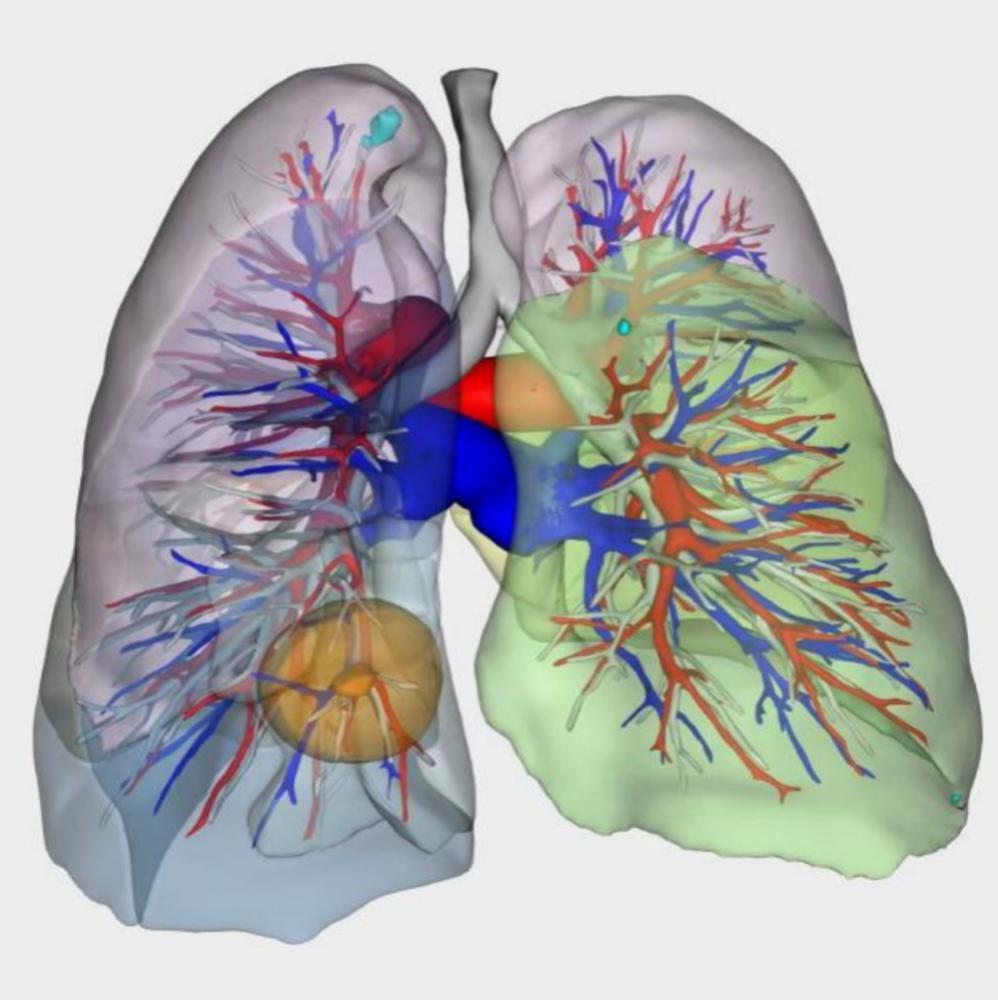

技术二:术前肺3D重建,尽可能保留肺功能

谢建将表示,医生会根据肺结节所在的位置不同,切除肺小结节一般有两种方式:1、肺楔形切除(部分切除,比如肺结节长在肺叶的边缘);2、肺段切除(当肺结节分布在肺段内,距离肺段分界有一定距离时,可依据3D重建的数据,判断动脉血管位置,进行解剖性切除)。

经3D重建后的效果图谢建将说:“在3D重建图中,医生可直观看到肺内支气管、动静脉等肺段解剖结构,根据不同个体差异进行专业化定制,依据重建后的分段,进行体积更小、更精准切除,尽可能保留肺功能,降低手术对生活的影响。”

胸外科术中利用肺3D重建图像,进行精准肺段切除